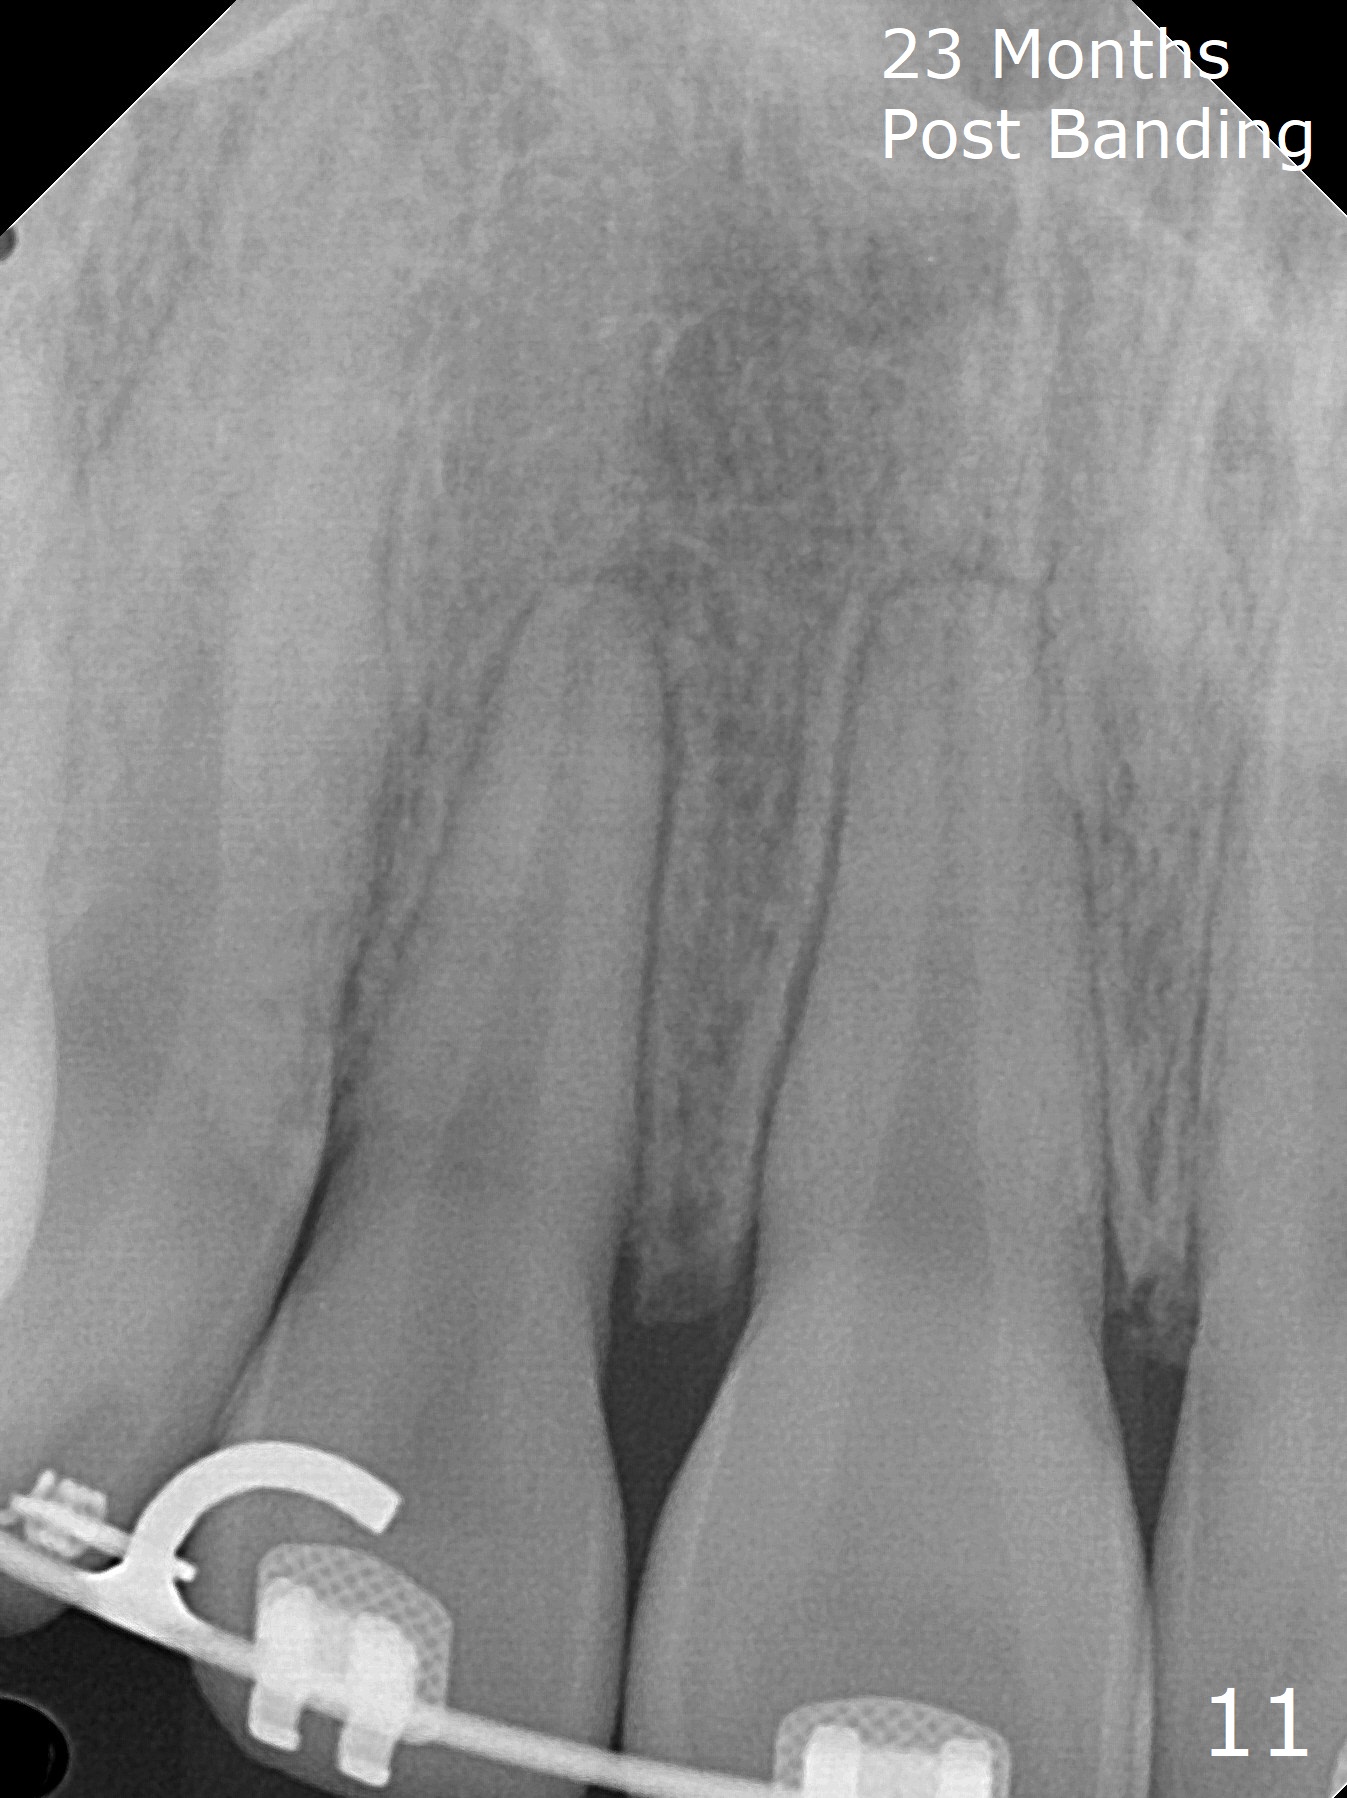

Anterior overbite and overjet and posterior interdigitation are satisfactory, while the roots of the upper incisors look shortened 23 months post banding (Fig.11,12, as compared to pre-banding (Fig.13). Brackets and bands are removed.